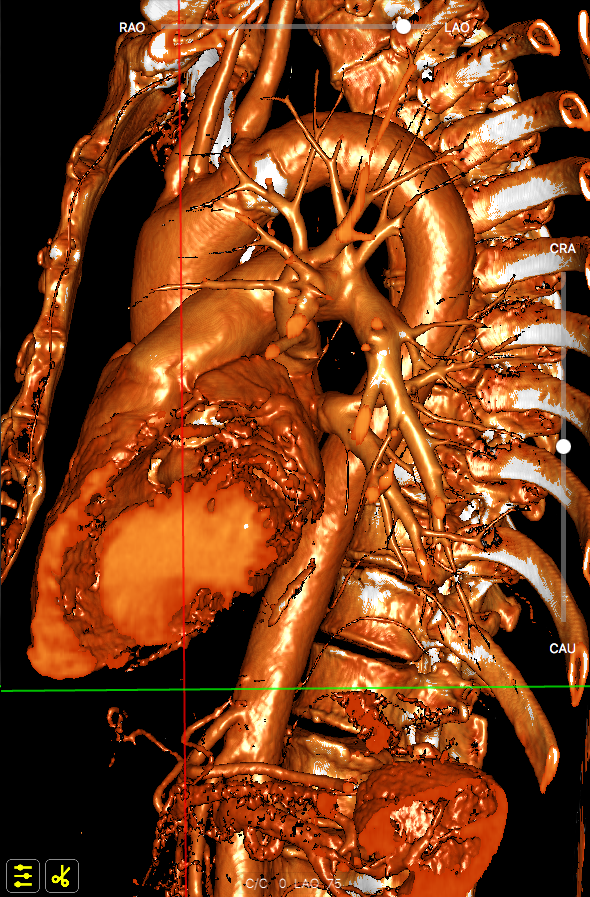

主动脉根部数据:

主动脉瓣环周长82.2mm(平均直径26.1mm),流出道周长89.6mm(平均直径28.5mm),左冠高度:15.4mm,右边冠高:14.9mm,主动脉窦宽28.7mm/33.7mm/34.9mm、STJ周长:93.5mm(平均直径29.7mm)高度22.2mm,升主动脉周长:111.7mm(平均直径35.5mm)。

术前心胸外科、心血管内科、超声科、麻醉科、体外循环、介入室等科室进行了术前讨论和术前策略分析:该患者主动脉瓣属于钙化狭窄的Type0型二叶瓣,左右冠脉同窦,无冠窦可见团状钙化,左右同窦钙化相对较少,主动脉瓣环周长82.2mm、呈现椭圆形,左室流出道周长89.6mm,主动脉窦宽28.7mm/33.7mm/34.9mm、窦宽可,STJ周长93.5mm、高度22.2mm,升主动脉周长111.7mm。患者心室壁明显增厚心尖较薄。左冠高度15.4mm右冠高度14.9mm,双冠高度可。患者右股动脉分叉点位于股骨头下缘,穿刺点内径为8.1mm,血管无明显钙化轻度迂曲。左股动脉分叉点位于股骨头下缘,穿刺点内径为7.8mm,血管无明显钙化轻度迂曲。选择右侧股动脉为主入路,左侧股动脉可作为辅入路;考虑患者主动脉瓣二叶式畸形,钙化严重,采用DOWNSIZE策略,综合评估选择20mm/22mm球囊预扩;患者瓣环周长82.2mm,考虑TAV27型号瓣膜。